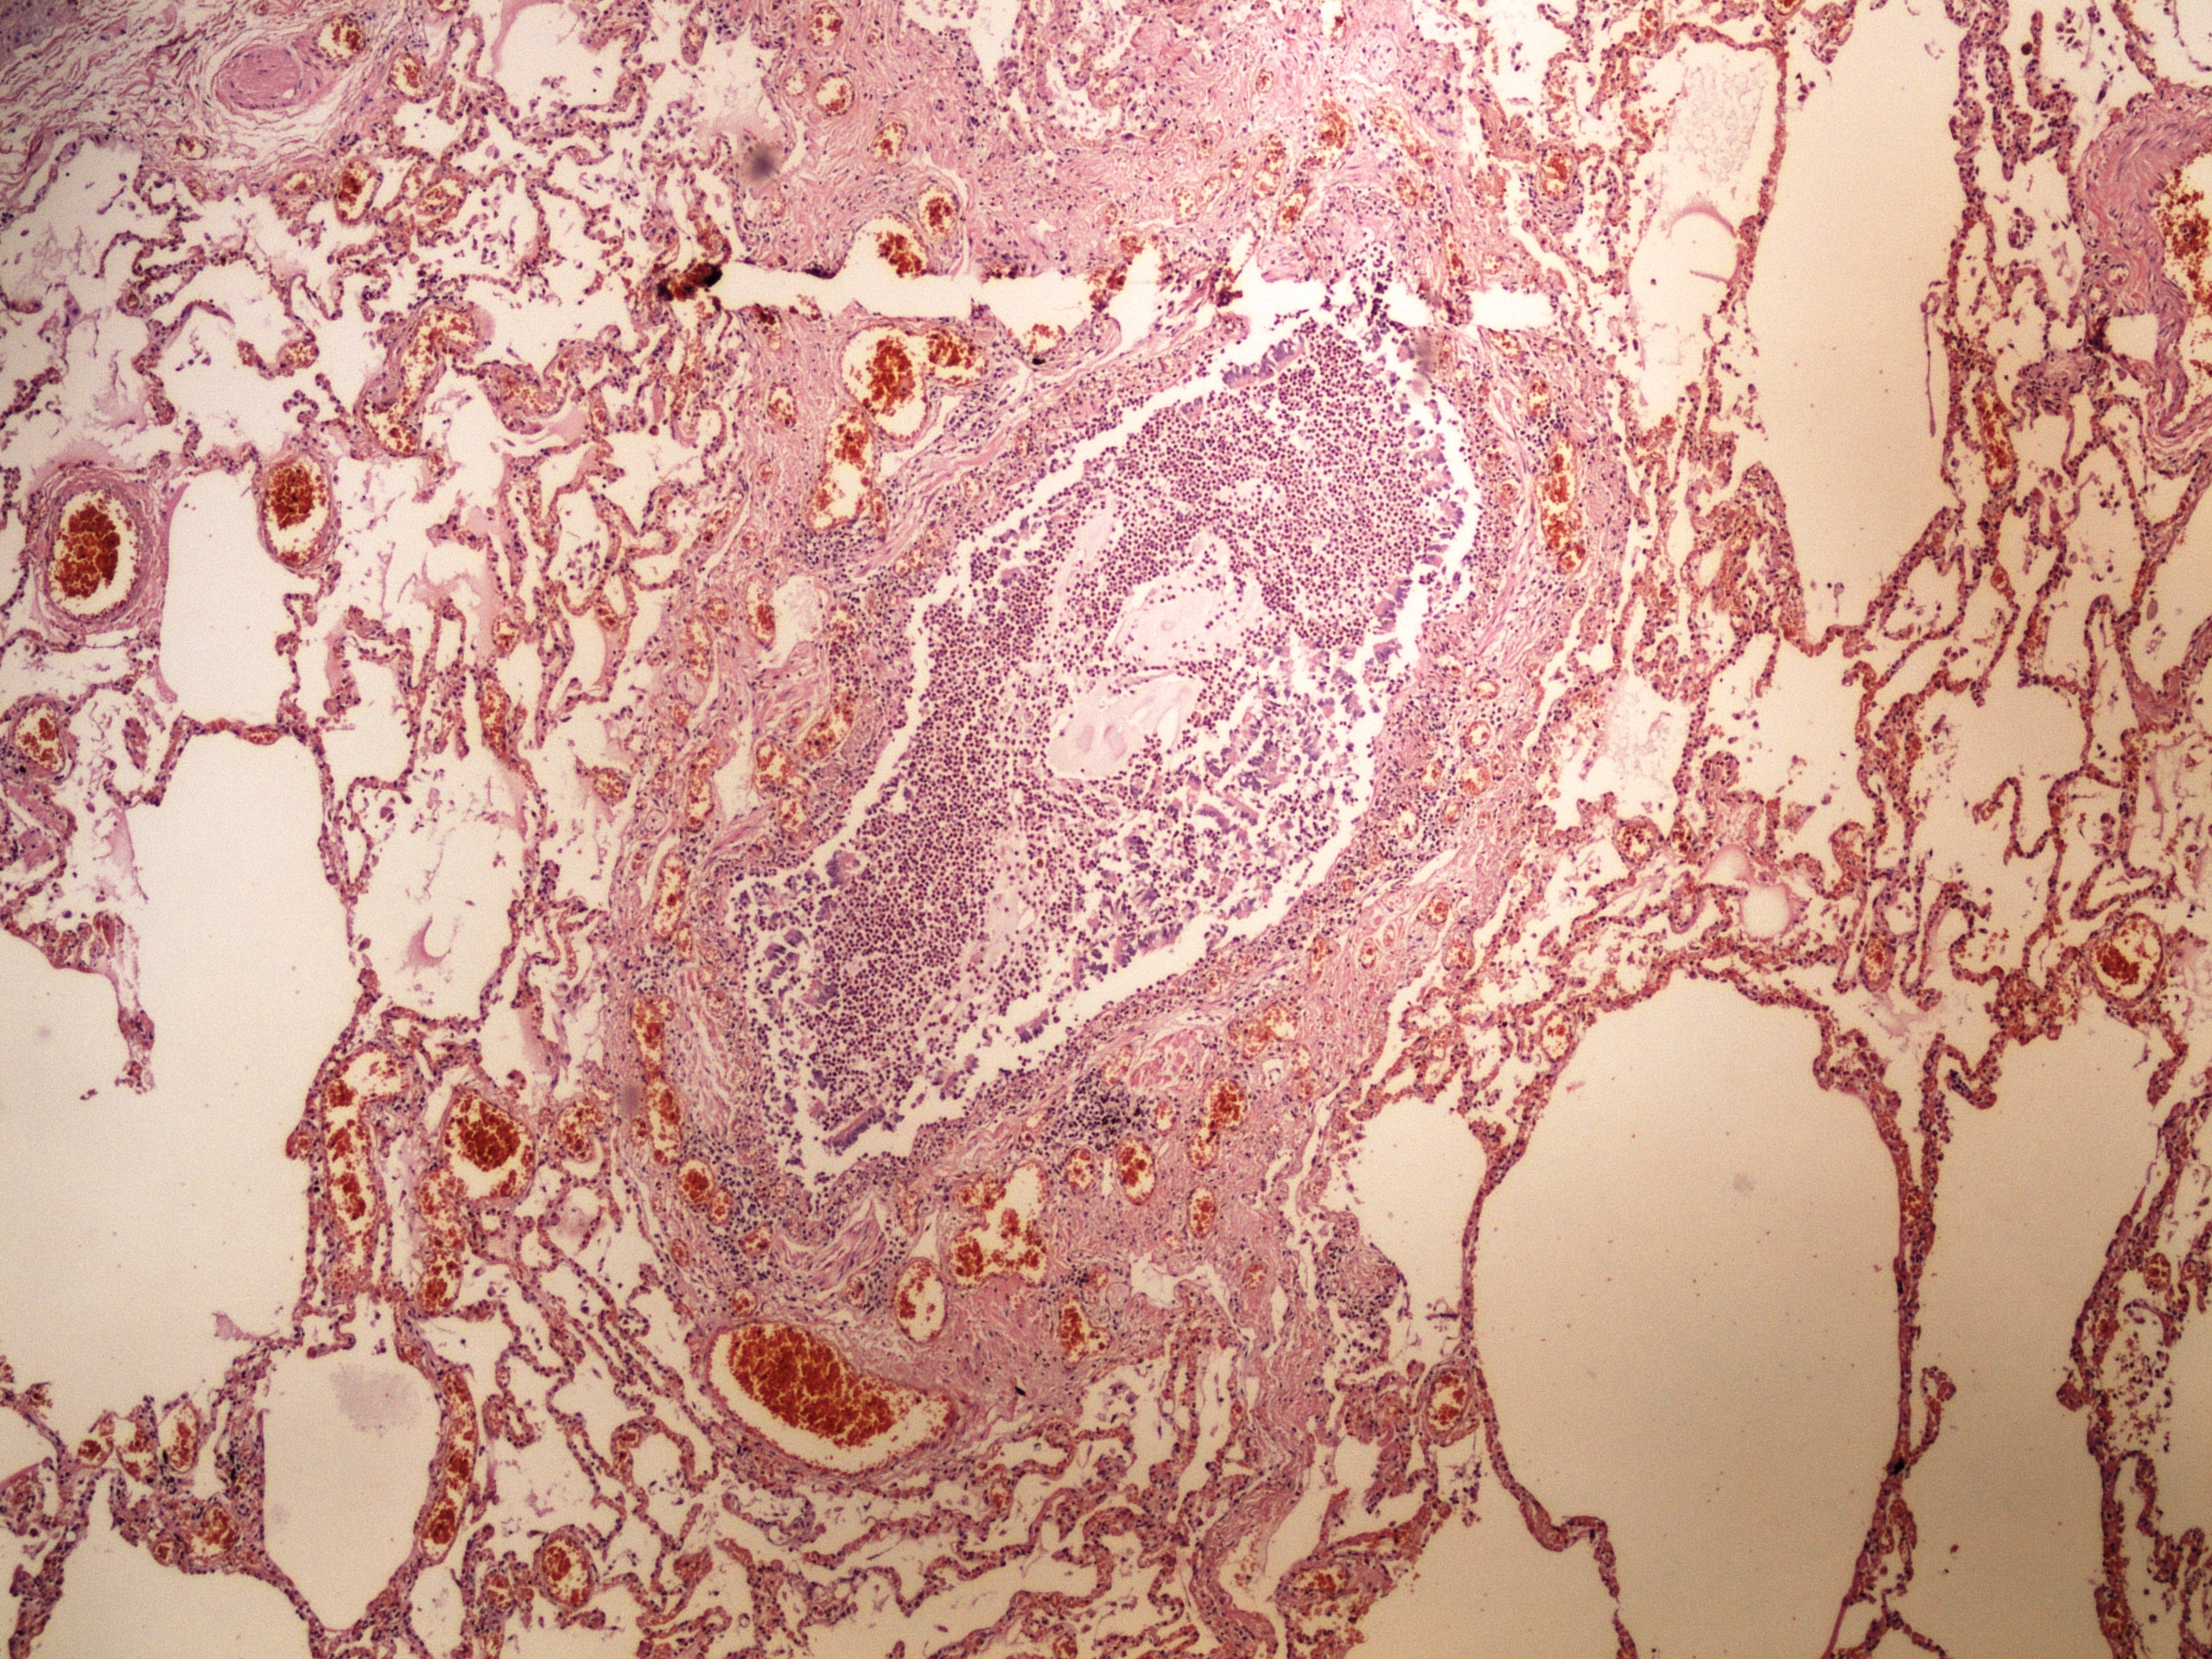

Preparát č.9 a č.10 - chronický plicní absces

Struktury

- nespecifická granulační tkáň